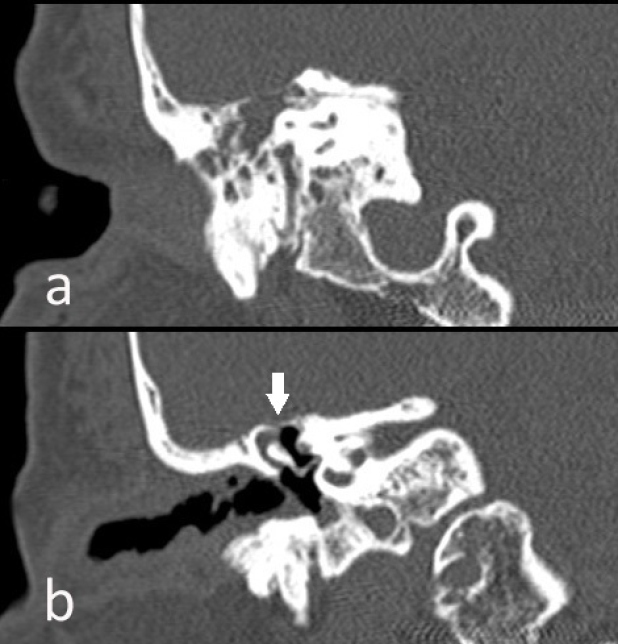

Presentamos imágenes de una paciente de 65 años en estudio por otalgia derecha con pérdida completa de la audición tras proceso gripal, con implante de tubo de drenaje transtimpánico. Posteriormente, inició otorrea abundante de líquido transparente, instaurándose tratamiento antibiótico ante la posibilidad de fuga de LCR. Mediante TC craneal se identificó una ocupación del oído medio, espacio de Prussak y receso hipotimpánico, con erosión del scotum y del tegmen timpani por probable colesteatoma (figura 1b, flecha). La exploración neurológica no demostró afectación meníngea, realizándose una cisternogammagrafía isotópica con 111In-DTPA ante la persistencia de la otorrea y sospecha de fístula de LCR, presentando actividad intensa del radiofármaco en oído derecho y en todos los tapones óticos (figura 2A, flecha). Una RNM cerebral posterior no mostró signos de encefalocele ni meningocele (figura 2B, flecha). Tras la confirmación de la existencia de fuga de LCR se instaló un drenaje externo lumbar conectado a circuito de depósito hermético y estéril, cediendo la otorrea, sin requerirse intervención quirúrgica.